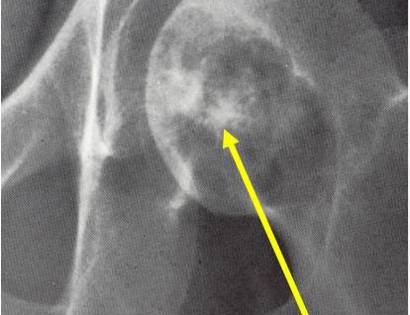

X-Ray of Clear Cell Chondrosarcoma

On an X-Ray, also called a radiograph, a clear cell chondrosarcoma can be diagnosed by looking at certain features. Most commonly seen in a clear cell chondrosarcoma is usually osteolytic, expansile lesion, that may be focally calcified, often a sharp interface between tumor and surrounding bone and the overlying cortex is usually thin, but intact.